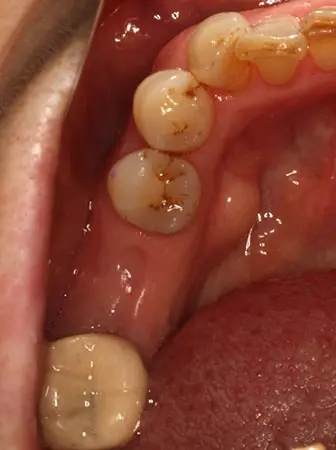

2024.12.1540代男性 天然歯をできる限り残すためにインプラントを用いながら虫歯の治療と噛み合わせを改善した症例